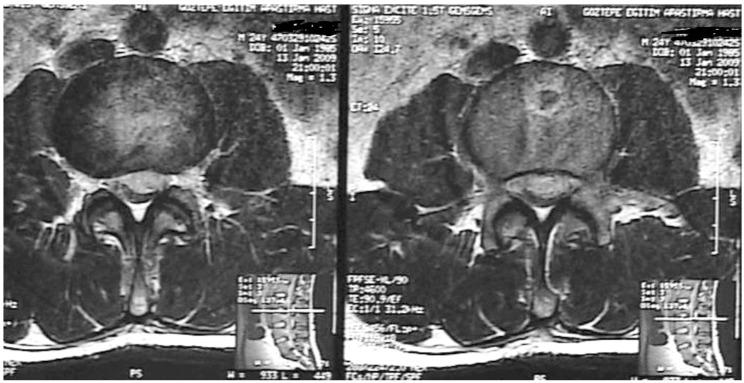

Pseudotumor cerebri is a condition of increased intracranial pressure in the absence of clinical, laboratory or radiological pathology. Spinal intradural hematoma formation after lumboperitoneal shunt (LPS) implantation is very rare, but it can cause sudden and serious deterioration. In this report, we present a patient who developed an intradural hematoma following LPS operation. A 27-year-old male patient suffering from headaches and progressive vision loss was diagnosed with pseudotumor cerebri. He underwent LPS operation in January 2009. Four hours after the operation, he developed urinary and fecal incontinence with paraparesis (1/5). Lumbar magnetic resonance imaging identified an intradural hematoma at the level of L2-L3, and he was reoperated. The intradural hematoma was removed. Physical therapy was started because of paraparesis. Two months later, the patient's muscle strength had increased to 3/5. Surgeons must remember that, LPS implantation can cause a spinal intradural hematoma in a small percentage of patients, with catastrophic results.